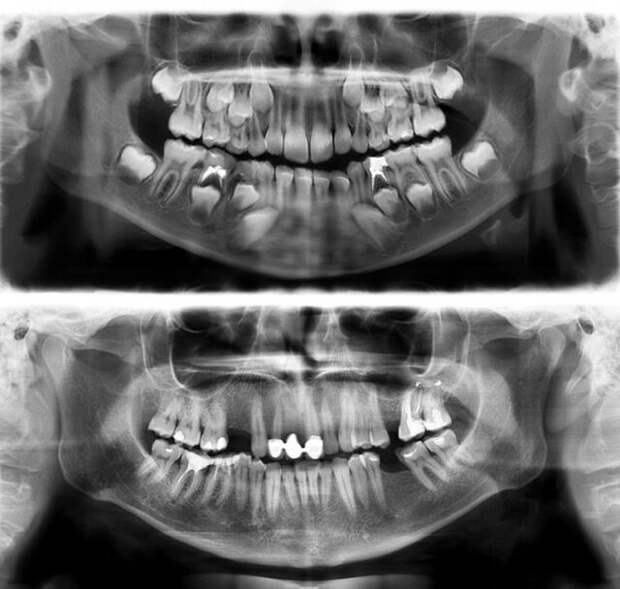

МРТ оперного певца  Зубы в семь лет и в тридцать

Зубы в семь лет и в тридцать  Мать и дитя в МРТ сканере